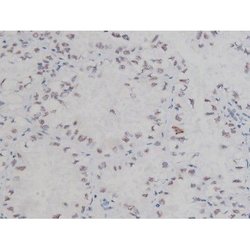

Invitrogen™ Phospho-NPM1 (Thr199) Polyclonal Antibody

Antibody detects endogenous levels of Nucleophosmin only when phosphorylated at Threonine 199.

| Applications | Immunohistochemistry (Paraffin), Western Blot, Immunocytochemistry |